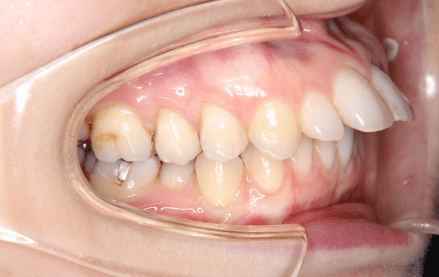

上顎前突は、いわゆる出っ歯の状態で奥歯をかみ合わせた状態で、上下の前歯が離れて前後的な隙間がある状態のことを指します。

上顎前突を放置するリスクとして、思春期のお子様では外傷のリスクが大きくなると言われております。また、唇が上下の前歯の間に挟まりやすいため唇を閉じにくく、乾燥により上あごの前歯が歯周病になるリスクが高かったり、唇が乾燥しやすくなったりすることもあります。